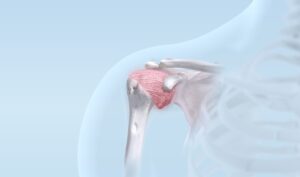

Rotatorenmanschette

Verletzungen der wichtigen Schultersehnen (Rotatorenmanschette) treten sehr häufig auf; durch den Funktionsverlust und schlafraubende Schmerzen in der Nacht wird die Lebensqualität erheblich beeinträchtigt.

Die Notwendigkeit und Machbarkeit einer Sehnenrekonstruktion werden in jedem individuellen Fall sorgfältig abgeklärt und abgewogen. Der Eingriff ist in den allermeisten Fällen in arthoskopischer Technik (Schlüssellochtechnik) ausführbar.

Neben der anspruchsvollen Operation erfordert insbesondere auch die erfolgreiche Nachbehandlung viel Erfahrung.